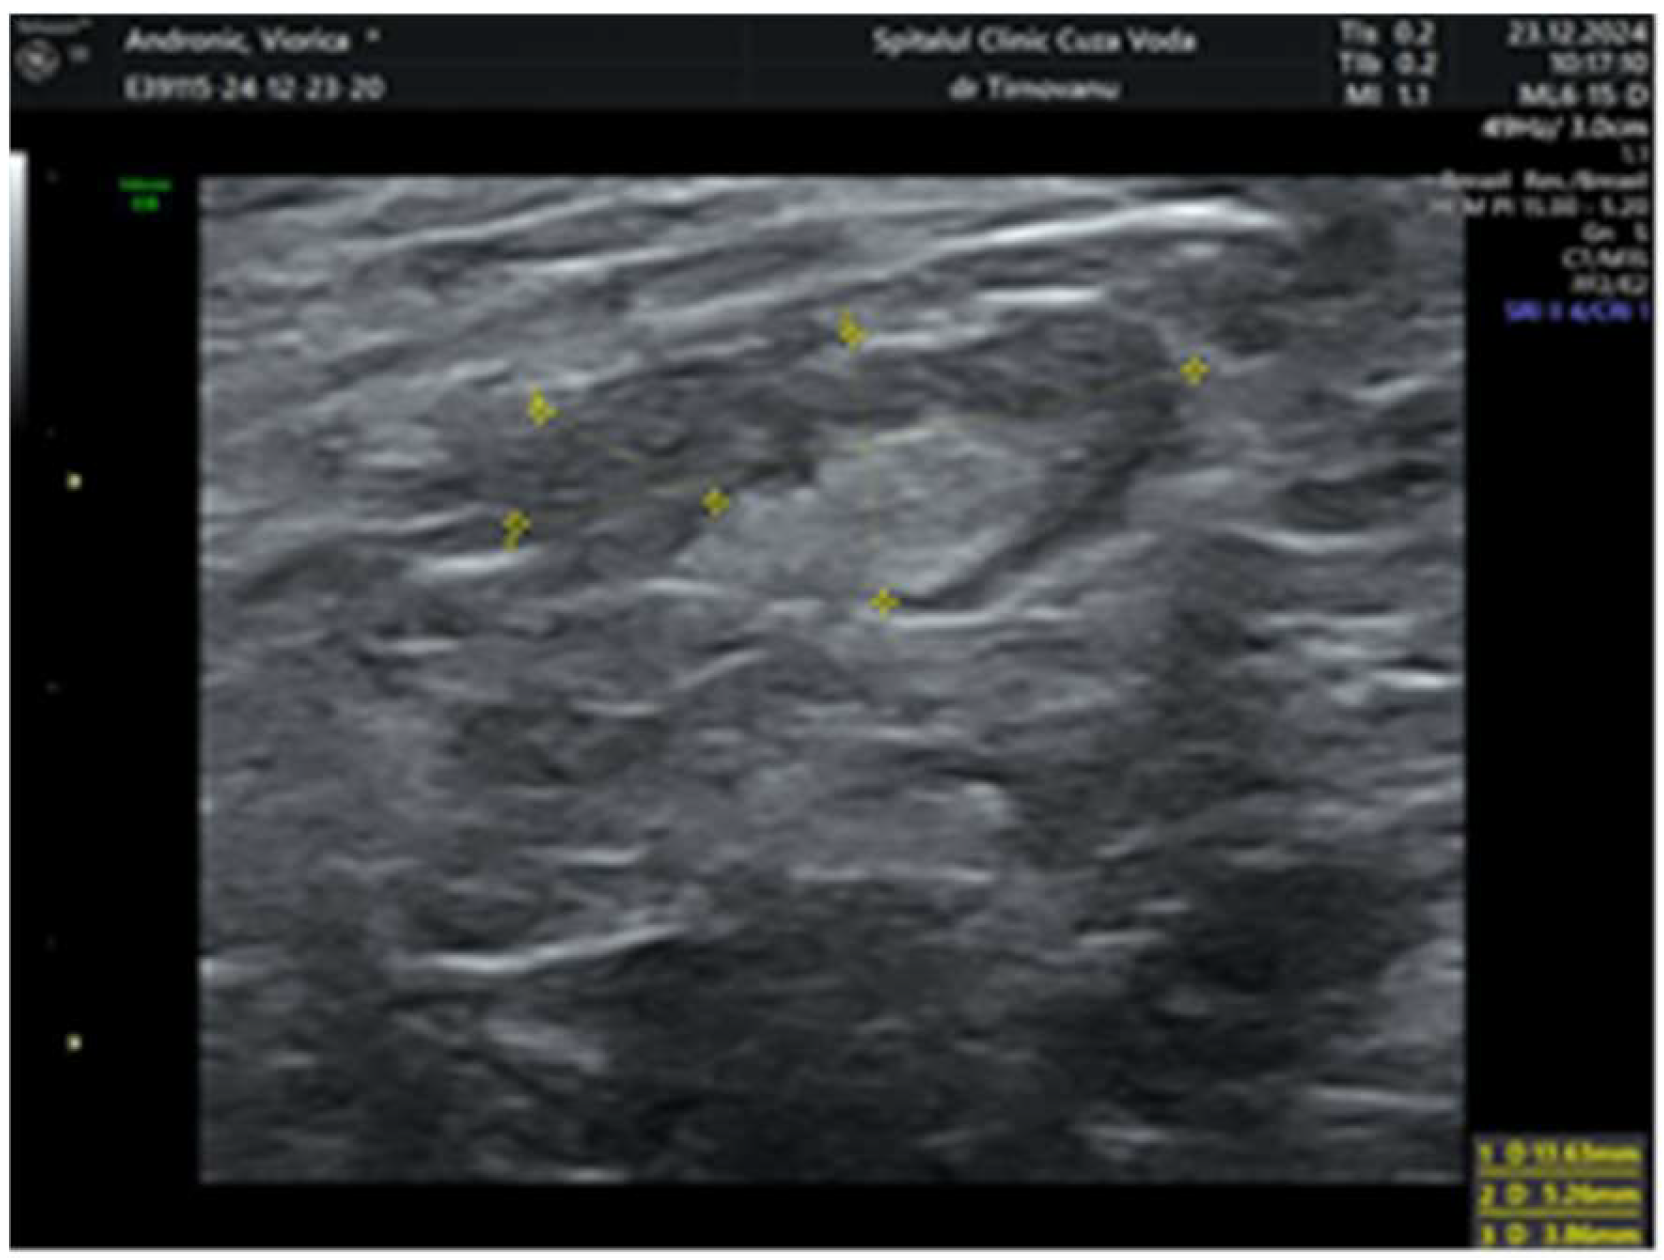

2. Case Report